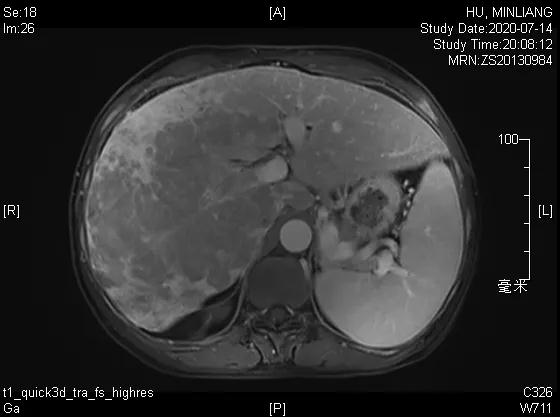

肝脏弹性超声:12kPa。腹部MRI平扫+增强:肝巨块结节性HCC(最大径18.4cm)伴肝内多发转移(最大径3.5cm),肝右静脉广泛癌栓形成;肝硬化伴门脉高压、脾大、少量腹水;肝囊肿;双肺多发转移。胸部CT平扫:两肺多发转移,两肺气肿伴肺大泡,两肺散在慢性炎症,右侧少量胸水。

Δ肝脏MRI,最大肿瘤18.4cm

肿瘤学评估(用药后2个月对比6个月):肝内主瘤明显缩小,动脉期强化降低;子灶消失;门脉右支癌栓明显缩小坏死;肺转移灶缩小,大部分消失。

2021-01-25

Δ治疗过程中病灶影像学变化